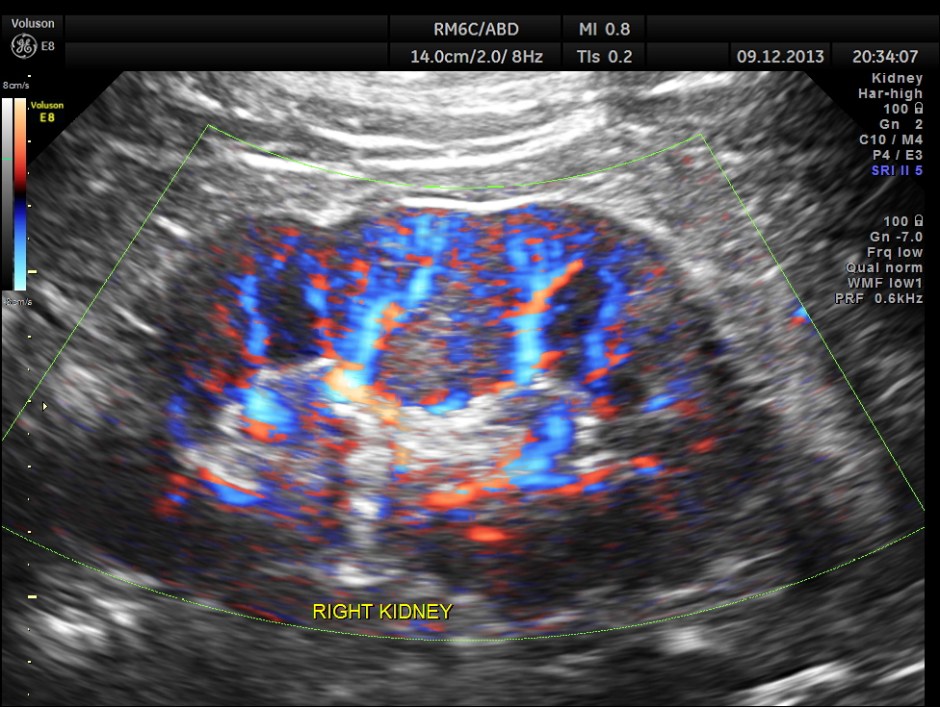

This patient was being evaluated for painless hematuria.

His right kidney appeared normal.

Power Doppler of the right kidney.